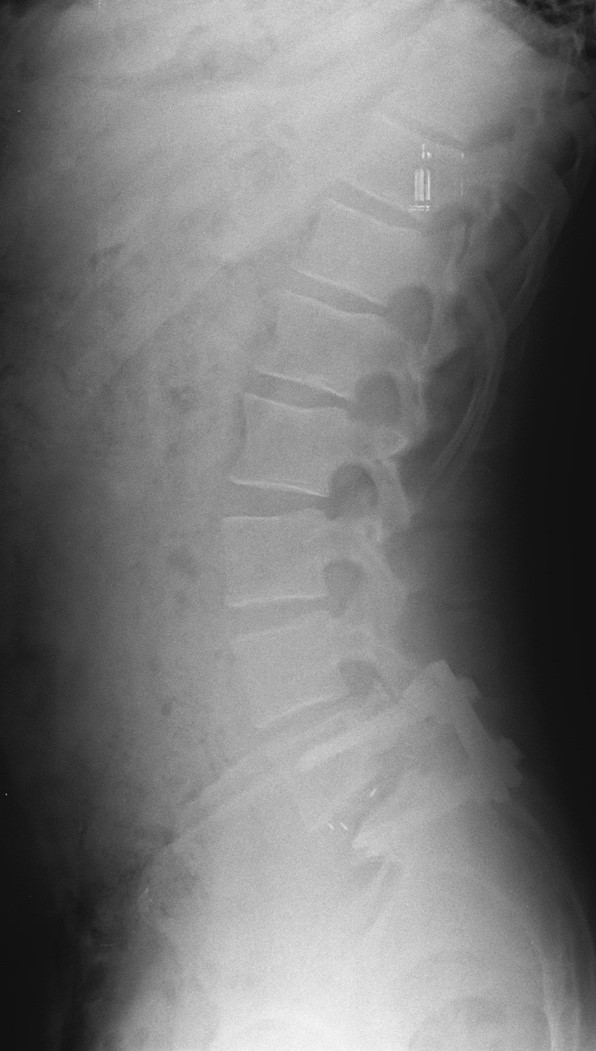

34 Yaşında Erkek Hasta

Low back pain

ODİ: %16

RM: 5/24

Ameliyat Öncesi